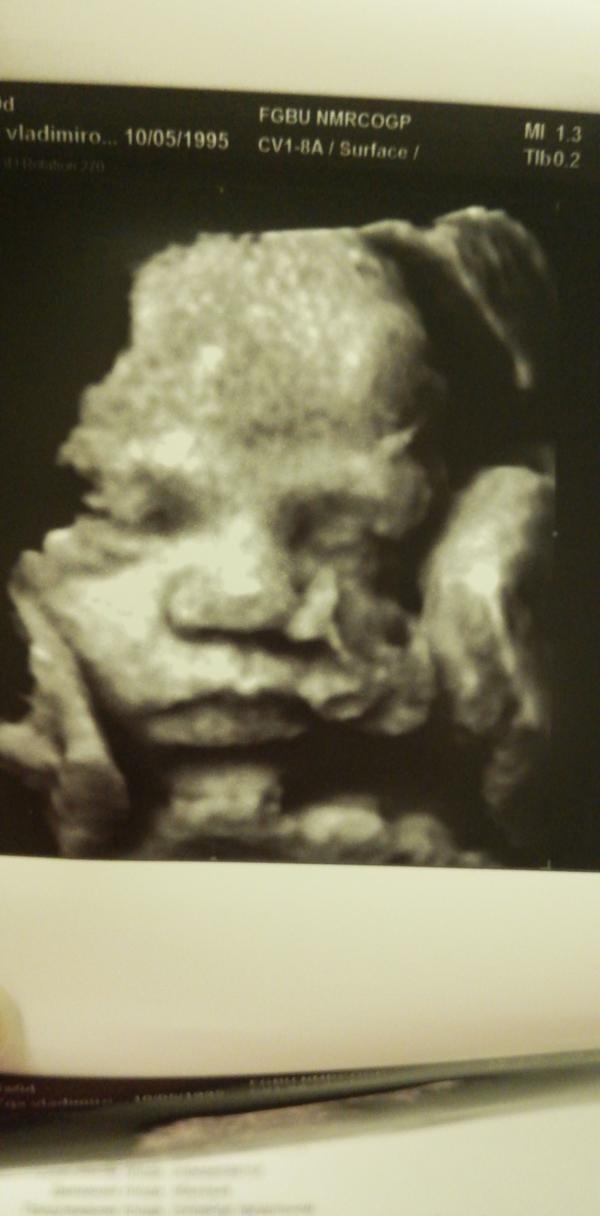

Сделали сегодня узи, ровно 31 неделя, по весу уже 1960 г) но зев закрылся, слава богу) через две недели повторное узи, так как теперь другая проблема - граница с многоводьем 🙄

Хороший какой